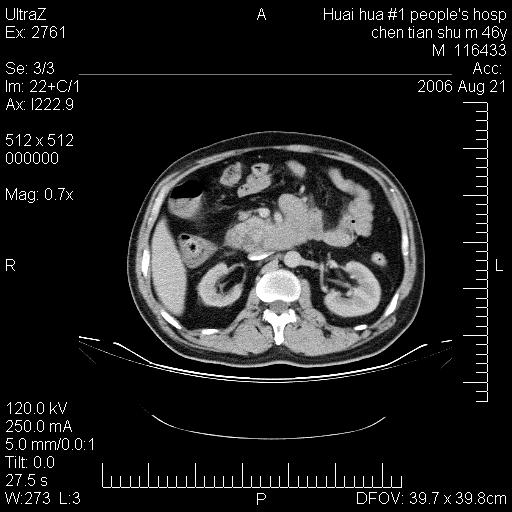

患者,男,46y。腹痛2月,消瘦。

十二指肠水平段占位,考虑间质瘤或平滑肌瘤。

肿块较大,腹膜后占位,境界欠清,周边脂肪密度较高呈条状影,有没有脂肪肉瘤可能,

缺少完整的三期图像。考虑肠系膜脂膜炎mp(肿块型)。

鉴别:间质瘤(这么大而无囊变不可思议)、平滑肌瘤/肉瘤、淋巴瘤、类癌,脂肪类肿瘤、转移瘤等。

十二指肠水平段占位,考虑间质瘤。

首先考虑小肠间质瘤。

十二指肠水平段软组织密度占位,考虑间质瘤可能性大。

腹膜后占位,境界欠清,考虑来源于十二指肠病变,间质瘤或平滑肌肉瘤可能性大。建议活检。

手术病理结果:原发性小肠恶性淋巴瘤(primary gastrointestinal lymphoma,pgil)是原发于胃肠的淋巴网织系统的恶性肿瘤,在结外淋巴瘤中居第一位,该病少见,临床无特异性,诊断困难,术前主要依靠影像学诊断。胃肠道本身具有较丰富的淋巴组织,因而胃肠原发性淋巴瘤是结外淋巴瘤最常见的部位,文献报道约占胃肠道恶性肿瘤的1%~4%,其中胃约占50%~70%,小肠约占35%~70%,结肠约占4%~6%。影像检查在pgil的诊断及分期中有重要的作用,ct是很有价值的检查方法。

胃肠淋巴瘤病理特点:胃肠道原发性淋巴瘤起源于胃肠壁固有层和黏膜下层的淋巴组织即胃肠粘膜相关淋巴组织(malt),多为粘膜相关淋巴瘤。病理上通常为非霍奇金淋巴瘤,且决大多数来源于b淋巴细胞,很少见于霍奇金淋巴瘤。胃肠原发淋巴瘤比胃肠道癌的发病率要低的多,最常见于胃,其病因可能跟幽门螺杆菌感染有关。幽门螺杆菌能引起胃粘膜损害,引起炎性及免疫反应,淋巴细胞聚集并形成滤泡,可影响胃的正常生理功能,导致胃淋巴瘤的发生。单纯性小肠淋巴瘤是常见好发于回盲末端,受累的肠段较长,可单发、多发,甚至累及整个小肠。原发性大肠淋巴瘤罕见,以直肠和盲肠最多见。病变大体观可表现为胃肠腔内外的肿块,也可表现为从黏膜下到浆膜面肠壁的纵向浸润,并且常常伴有肠系膜淋巴结肿大。任何情况下,肿瘤几乎总是导致一定程度的肠壁增厚,可对称或不对称,病变与正常组织间常无明确分界,肠腔可狭窄、正常或动脉瘤样扩张,后者主要是肿瘤在肠壁内浸润,破坏肠壁内植物神经丛所致。以上改变成为ct检测病变的病理基础。

肠道淋巴瘤的ct表现分为4类

1) 壁内浸润型, (2)多发结节型, (3)肠系膜受累伴腔外肿块型(本型就是),(4)肿块型。